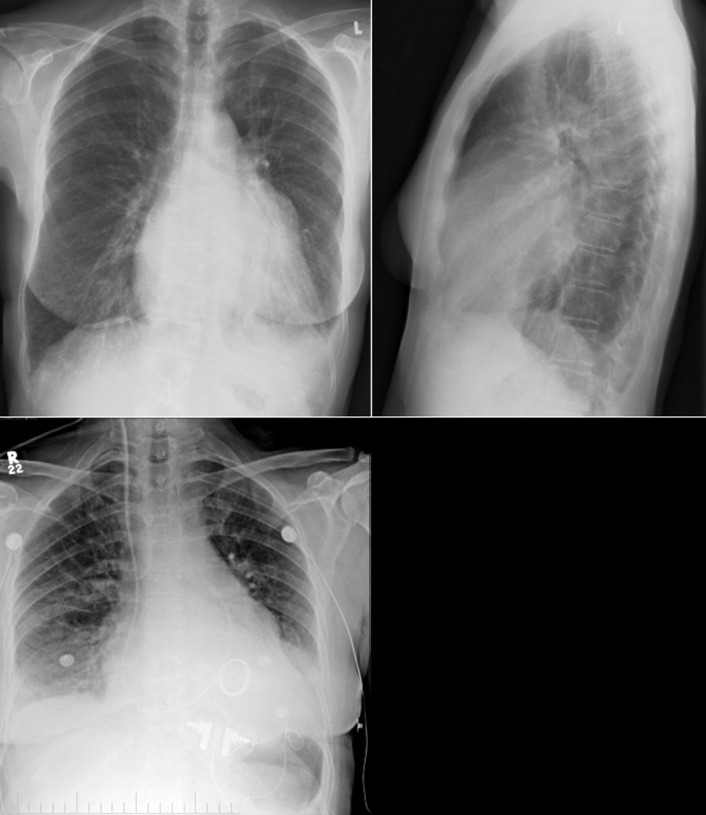

The radiographic findings of mitral stenosis ( Graphic 15-1 ; Figs. 15-1 to 15-16 ) reflect the pressure overload of the left atrium and pulmonary veins, and later of the right heart. As well, the commonly associated chronic atrial fibrillation contributes to (bi)atrial dilation. Associated rheumatic valvular lesions such as mitral regurgitation, tricuspid regurgitation, aortic insufficiency, and aortic stenosis/aortic insufficiency are common, and they alter the appearance of the heart.